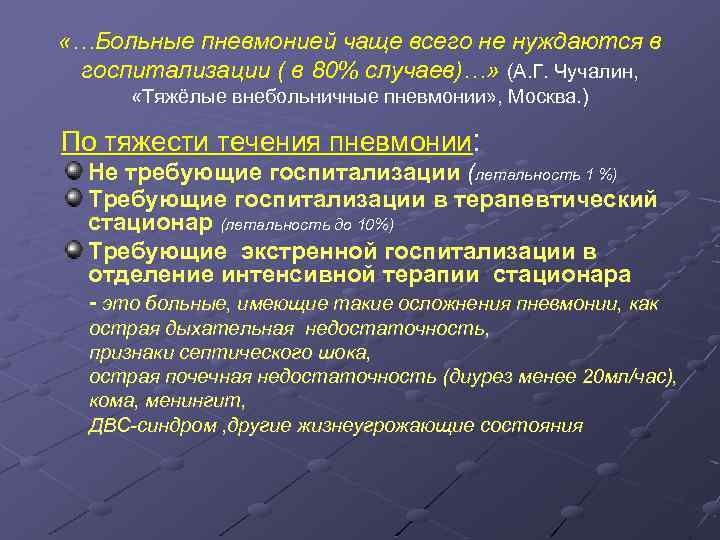

Острая внебольничная пневмония по МКБ-10: признаки и примеры